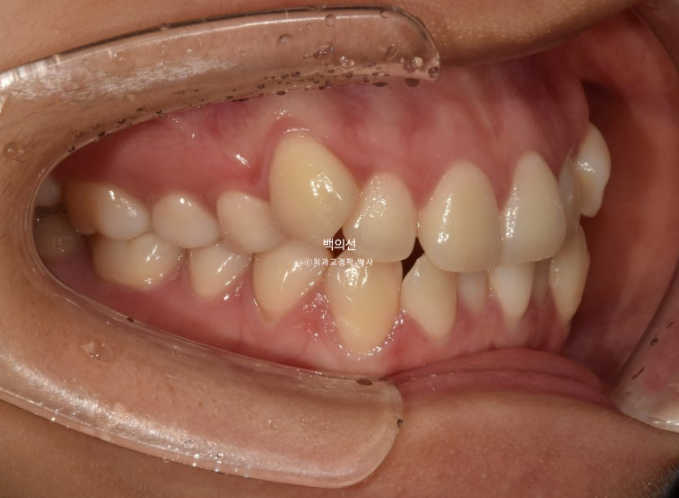

초진 입매를 보면 입술돌출은 거의 없지만 상기의 이유로 작은어금니 4개 발치교정을 결정하였습니다

환자분은 치주건강상의 이슈로 발치의 이유는 납득을 하지만 발치로 인해 입이 너무 들어가지 않게 해달라고 요청하셨습니다.

클리피씨 선택 후 치료에 들어갑니다.

치료 기간 내내 앞니가 뒤로 들어가는 것을 최소화 하고자 발치공간으로 어금니를 하나씩 앞으로 당겨오는 치료를 했습니다.